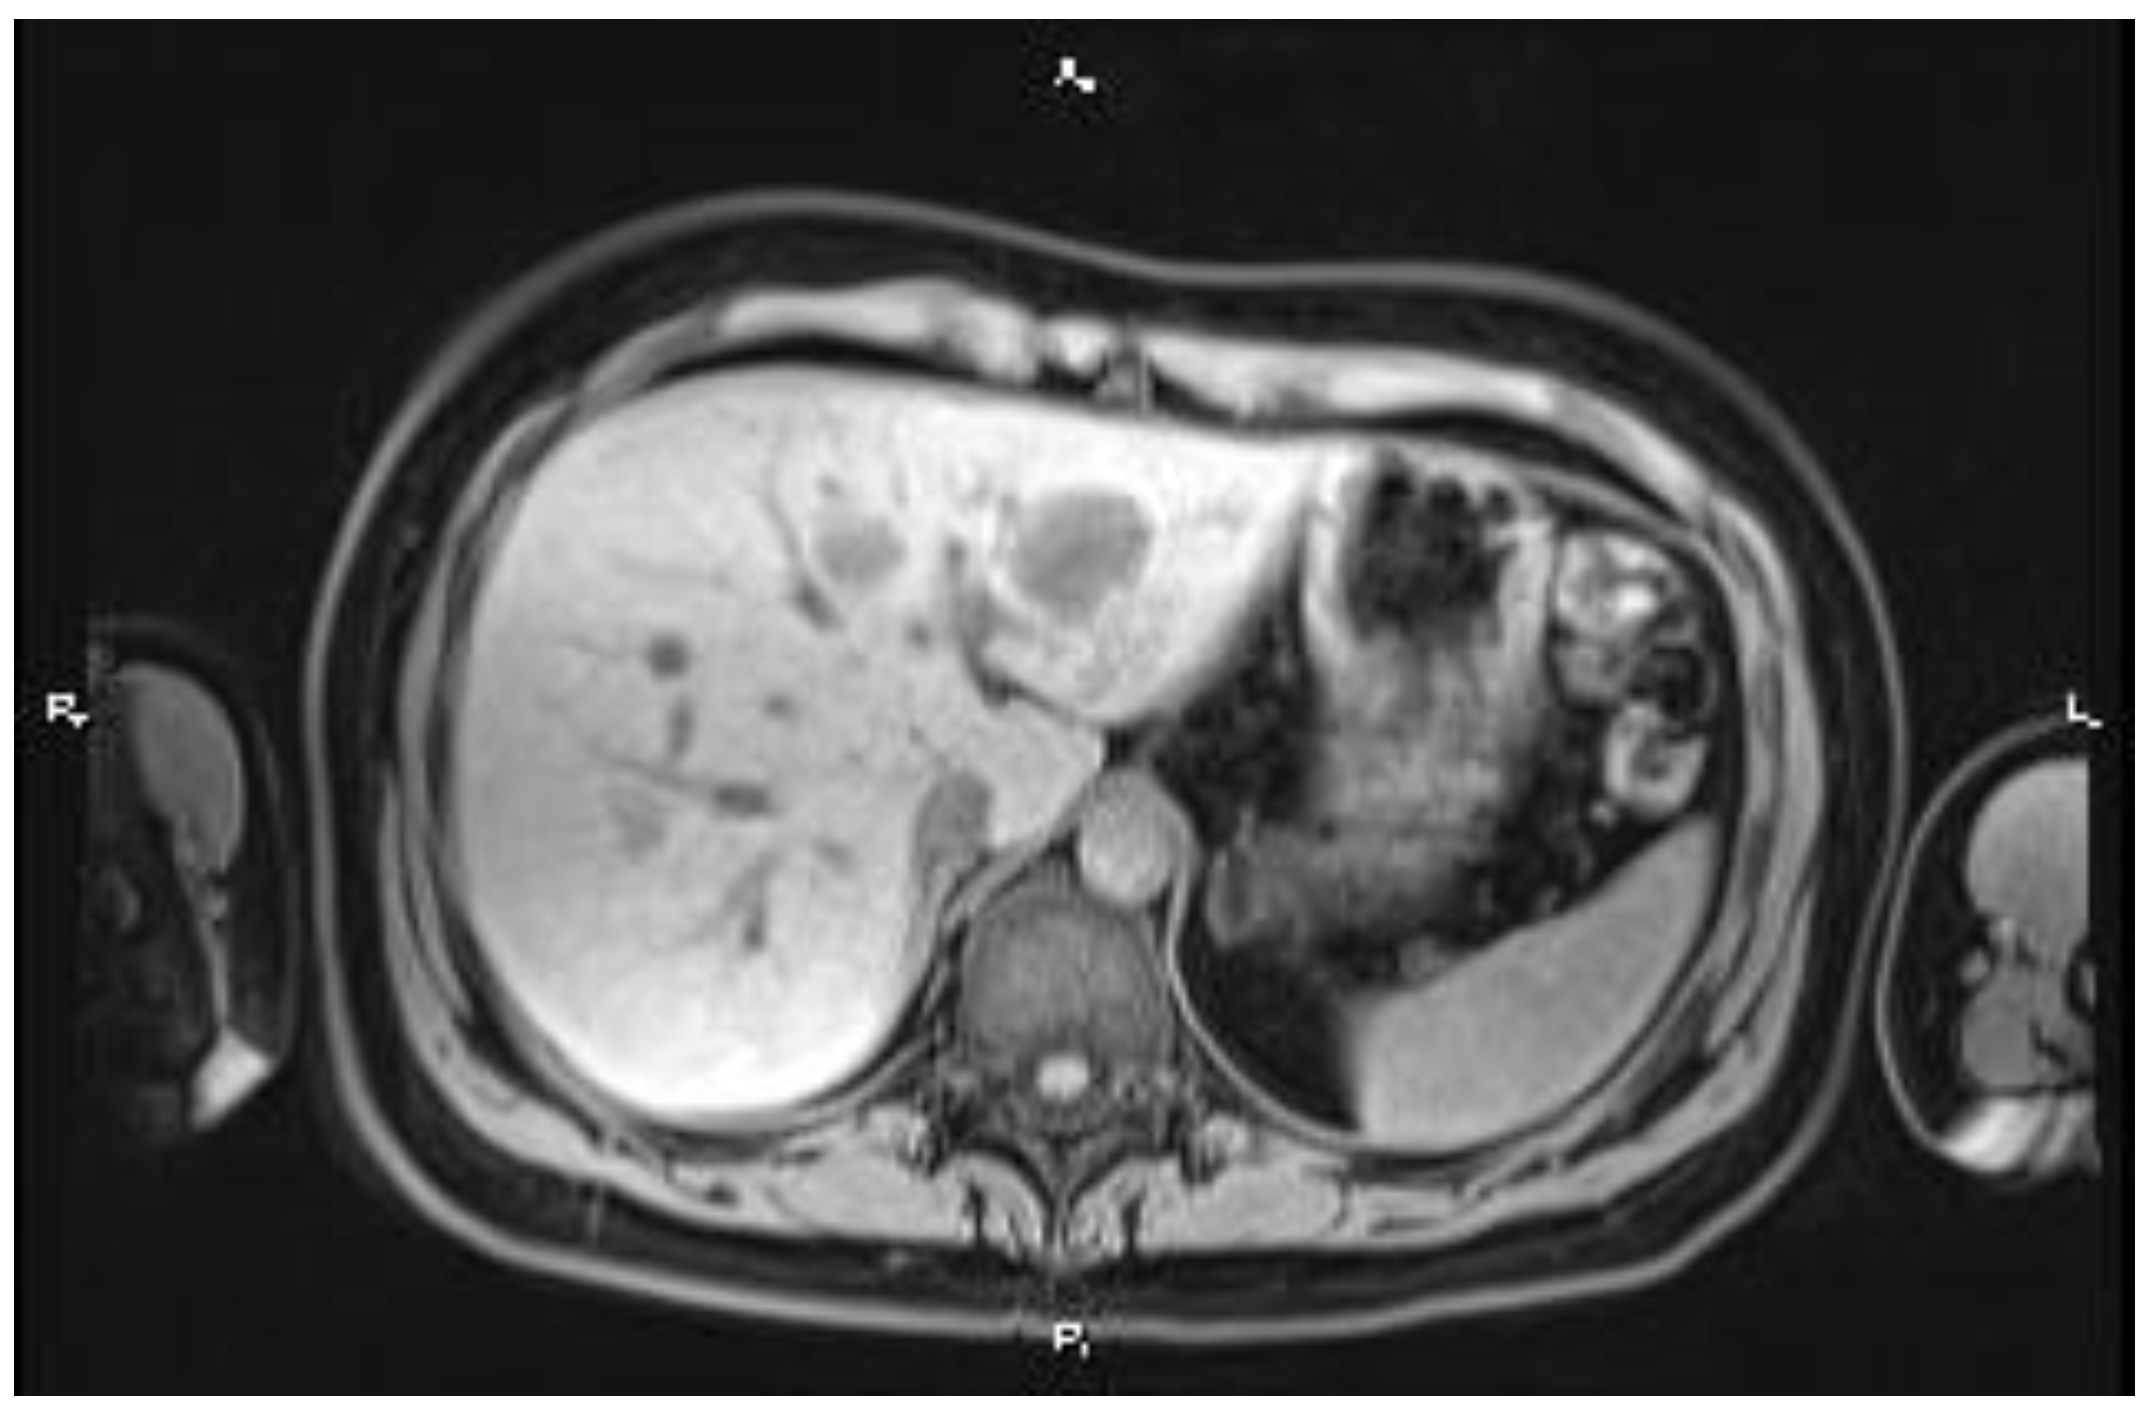

2. Case Report